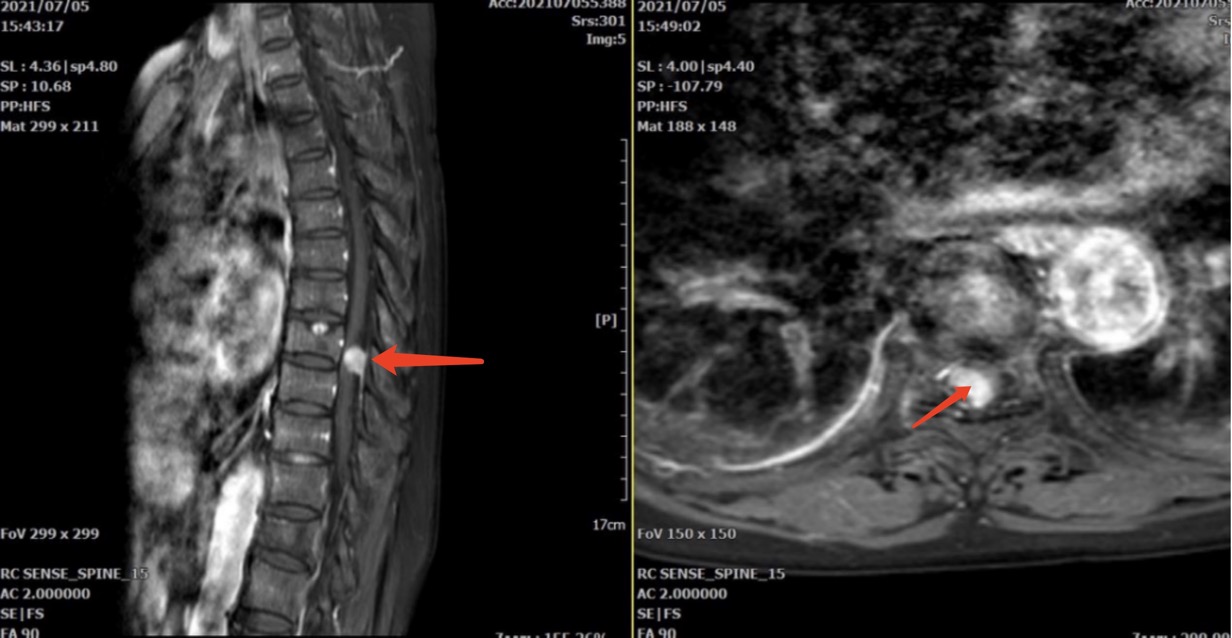

骨傷科副主任王慶敏詳細(xì)診查后,考慮葉阿婆的癥狀為胸8/9椎管水平的脊膜瘤壓迫脊髓神經(jīng)引起。增強磁共振清楚顯示椎管內(nèi)占位面積已經(jīng)超過80%,手術(shù)指征明確。由于胸椎管狹窄、手術(shù)操作空間小,損傷脊髓神經(jīng)的風(fēng)險極高,如術(shù)中止血不徹底,術(shù)后血腫壓迫也會導(dǎo)致患者癱瘓。

經(jīng)過縝密的術(shù)前規(guī)劃,王慶敏團隊決定對患者實施“天璣”骨科機器人輔助下后路胸8-9椎弓根釘內(nèi)固定+超聲骨刀后壁切除減壓+腫瘤摘除術(shù)+外側(cè)植骨融合術(shù)。手術(shù)過程順利,術(shù)中出血不足100ml,術(shù)后患者雙下肢肌力由2級提升為4級。葉阿婆又能自主行走了。